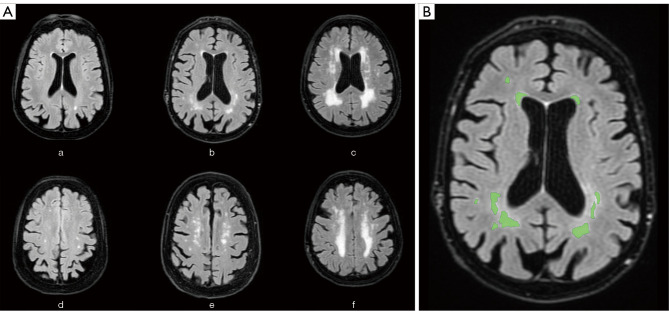

Background: This systematic review summarizes available evidence on the relationship between white matter hyperintensities (WMH) volumetric quantification on brain MRI scans and chronic kidney disease (CKD).

Conclusions: Literature on this topic is extremely heterogeneous in terms of methodology and samples. However, evidence shows that there is a relationship between CKD and WMH volume of the brain. We recommend that quantifiable biomarkers such as estimated glomerular filtration rate (eGFR) and urine albumin to creatinine ratio (UACR) should be included in studies dealing with cerebrovascular disease. The biological and molecular mechanisms underlying cerebrovascular damage in patients with chronic renal failure deserve to be further explored.